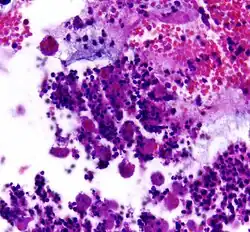

![]() |

Diffuse B-cell lymphoma | Lymph node FNA specimen showing diffuse large B cell lymphoma. | Category: Histopathology of diffuse large B cell lymphoma | Diffuse large B-cell lymphoma |